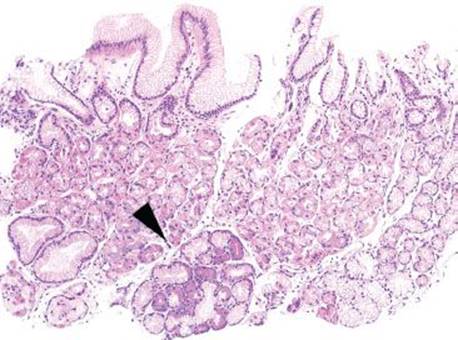

ATROPHIC

The definition of “atrophy” is the loss of appropriate glands, and atrophy can be scored according to the degree of severity as mild, moderate, or marked (Figs. 2.99–2.105). Atrophy can be divided into antral/pyloric gland atrophy, and oxyntic gland atrophy. By definition, both AMAG and EMAG have glandular atrophy, but in differing compartments.

Figure 2.103 Chronic gastritis pattern, partial oxyntic gland atrophy, early AMAG. This inflamed mucosa can appear quite “busy”, but careful examination reveals areas of oxyntic gland loss/atrophy (arrowheads; residual oxyntic glands in bracket). Patchy atrophy of oxyntic glands such as this should raise suspicion for early AMAG.

Compartment, Atrophic Subpattern

Since AMAG is the result of oxyntic gland atrophy from antibodies against parietal cells, this disease process is, necessarily, limited to oxyntic mucosa. In contrast, EMAG is an antral-predominant disease process and results in antral atrophy before extending multifocally into the gastric body and fundus. Late stage disease for both entities provides some challenges, since total atrophy of oxyntic glands in late AMAG can deceive one into accepting the tissue as antrum. Alternatively, the late stage of EMAG can also show atrophy of oxyntic glands, misleading one into thinking there is an autoimmune process. Immunostaining for gastrin is a quick, and sometimes necessary, method to identify the site of origin for a biopsy fragment (the gastric antrum displays a band of G cells, and the gastric body/fundus lacks G cells). Identification of other compartment-restricted patterns of injury is necessary to establish a diagnosis.